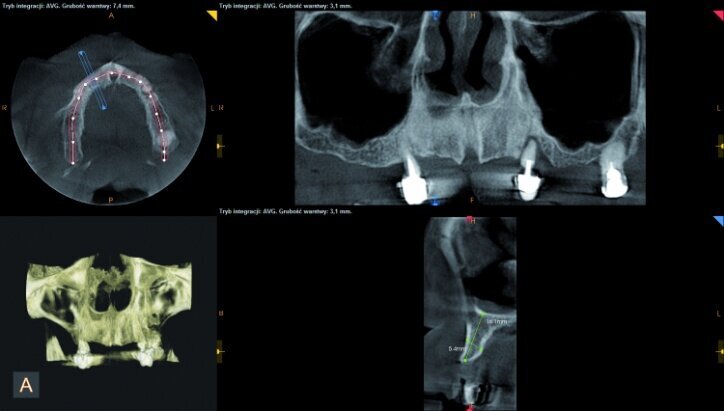

During the process of treatment planning, a few proposals for prosthetic solutions were presented, including permanent and temporary restorations, based on existing teeth as well as implants of various combinations. After analysing CBCT scans (Figs. 3–6) it could be concluded that implantological treatment may be performed at the front maxilla without any additional procedures, however, due to significant atrophy in the lateral part and a low-lying fundus of the left and right maxillary sinus, it appeared necessary to perform augmentation procedures (sinus lift), in order to make implantation possible.